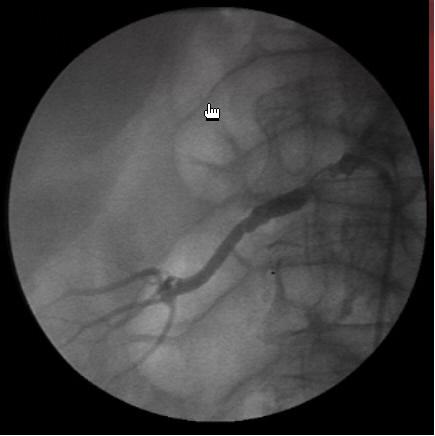

It presents with chronic abdominal pain and the diagnosis is often missed because of nonspecific clinical findings mm Cordis Genesis stent and IMA ostium with 3mm x 13mm Cordis Cypher stent after balloon dilatation (angioplasty) at ... Read Document

Peripheral Procedures In The Cardiac CathLab National AAPC ...

Peripheral Procedures in the Cardiac CathLab National AAPC April 2, 2012 Presented by: David Zielske, MD (including , abdominal aortography, pressure gradients, ... Doc Retrieval

Multislice CT Virtual Intravascular Endoscopy For Abdominal ...

Multislice CT Virtual Intravascular Endoscopy for Abdominal Aortic Aneurysm Stent Grafts (SMA), renal ostium, and aortic aneurysm. RESULTS: Image quality of VIE images was independent of section thickness and pitch values in the level of renal ... Access Full Source

Endovascular Repair Of An Abdominal Aortic Aneurysm

He was subjected to an abdominal ultrasound, which revealed the presence of an infrarenal abdominal aortic aneurysm with a diameter of approximately 7 cm. right renal artery ostium and optimize proximal landing. The procedure was completed by introducing the right contralateral leg ... Document Viewer